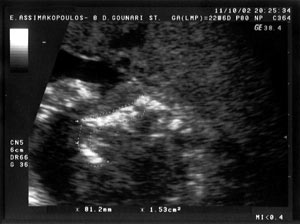

3.

4.

Εικόνα

3. Στην περίπτωση 1 διακρίνεται το έμμεσο υπερηχογραφικό εύρημα σχήματος

σταγόνας δακρύου (tear drop shape) από τη διάταση των πλαγίων κοιλιών, στην

κλασική εγκάρσια διατομή απεικόνισης των πλαγίων κοιλιών και μέτρησης των BPD,

OFD και HC.

Έγκυος ηλικίας 31 ετών, πρωτοτόκος, προσήλθε για υπερηχογράφημα δευτέρου επιπέδου

στις 22 εβδομάδες της κύησης. Η βιομετρία του εμβρύου ήταν φυσιολογική. Φυσιολογική

ήταν επίσης και η ανατομία του εμβρύου από όλα τα συστήματα, με εξαίρεση την

ανατομία του εγκεφάλου που παρατηρήθηκε απουσία του μεσολοβίου. Στην εικόνα

2 διακρίνεται η απουσία του μεσολοβίου σε οβελιαία διατομή (σύγκρινε με εικόνα

1), ενώ στην εικόνα 3 διακρίνεται το έμμεσο υπερηχογραφικό εύρημα σχήματος σταγόνας

δακρύου (tear drop shape) από τη διάταση των πλαγίων κοιλιών, σε εγκάρσια διατομή.

Το δεύτερο σημείο-κλειδί, στην εγκάρσια διατομή, στο υπερηχογράφημα δευτέρου

επιπέδου που υποδηλώνει την αγενεσία του μεσολοβίου είναι το λεγόμενο σημείο

της σιδηροδρομικής γραμμής (railroad track sign). Πρόκειται για δύο ζεύγη γραμμών

που βρίσκονται πολύ κοντά η μία στην άλλη, εκατέρωθεν της μέσης γραμμής. Αυτό

το εύρημα μαζί με τη συχνά παρατηρούμενη διάταση των κόλπων των πλαγίων κοιλιών

δίνει στις πλάγιες κοιλίες το χαρακτηριστικό σχήμα σταγόνας δακρύου (tear drop

shape) (εικόνες 3,6).